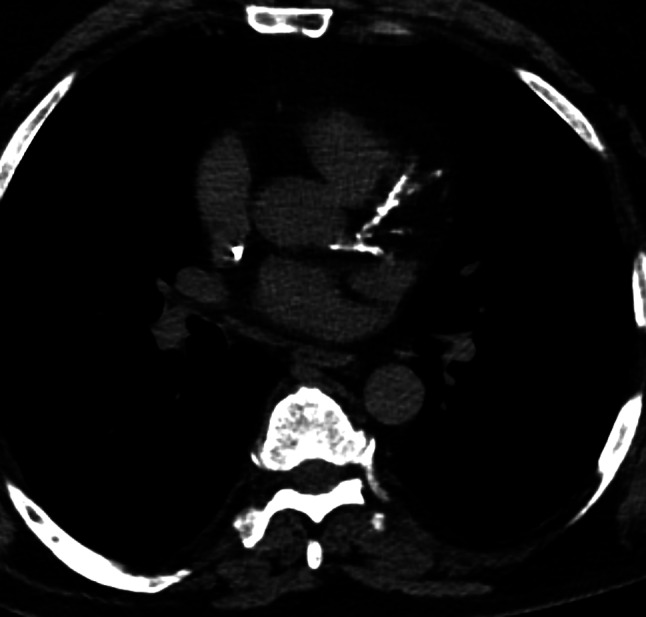

背景:冠状动脉钙化(CAC)评分可以作为计算机断层扫描(CT)的副产品。CAC评分可以反映患者的心血管风险概况。本研究的目的是确定CAC对多发性骨髓瘤(MM)患者总生存期(OS)的影响。方法:回顾性分析2009 - 2019年所有行外周血干细胞移植的MM患者。共纳入127例患者,其中女性50例,占39.4%,平均年龄57.8±7.6岁。采用全身CT扫描评估每位患者的CAC评分。在非门控分期CT图像中应用Weston评分代替Agatston评分。c结果:共有27例患者(22.0%)在研究过程中死亡。在鉴别分析中,非幸存者和幸存者的CAC评分没有差异(平均1.2±2.4比2.0±2.8,p = 0.13)。CAC评分与总生存率无相关性,相对危险度为0.92 (95% CI 0.78-1.09, p = 0.35)。无钙化(CAC评分0分,n = 66, 51.9%)患者死亡18例,有钙化(CAC评分1分及以上,n = 61, 48.1%)患者死亡9例。Fisher精确检验结果显示两组间无统计学差异(p = 0.20)。结论:在接受自体干细胞治疗的年轻多发性骨髓瘤患者中,ct定义的冠状动脉钙化并不能预测其生存期,且生存期相对较短。在这种异质性疾病中,ct定义的心血管危险因素的影响似乎相对温和。

Methods: A retrospective analysis was conducted on all patients with MM undergoing peripheral blood stem cell transplantation between the years 2009 and 2019. A total of 127 patients (50 female patients, 39.4%) with a mean age of 57.8 ± 7.6 years were included in the analysis. A whole-body CT scan was used to assess the CAC score for each patient. The Weston score as a surrogate for Agatston score was applied in the non-gated staging CT images.c RESULTS: A total of 27 patients (22.0%) died during the course of the study. The CAC score did not differ between non-survivors and survivors in the discrimination analysis (mean 1.2 ± 2.4 versus 2.0 ± 2.8, p = 0.13). The CAC score showed no correlation with overall survival, with an HR of 0.92 (95% CI 0.78-1.09, p = 0.35). Of the patients without calcification (CAC score 0, n = 66, 51.9%), 18 died, while of those with calcification (CAC score 1 or higher, n = 61, 48.1%), nine died. The results of the Fisher's exact test showed no statistically significant difference between the two groups (p = 0.20).

Conclusions: The presence of CT-defined coronary calcifications does not predict survival in younger patients with multiple myeloma undergoing autologous stem cell therapy and comparably short survival. The impact of CT-defined cardiovascular risk factors appears to be relatively modest in this heterogeneous disease.